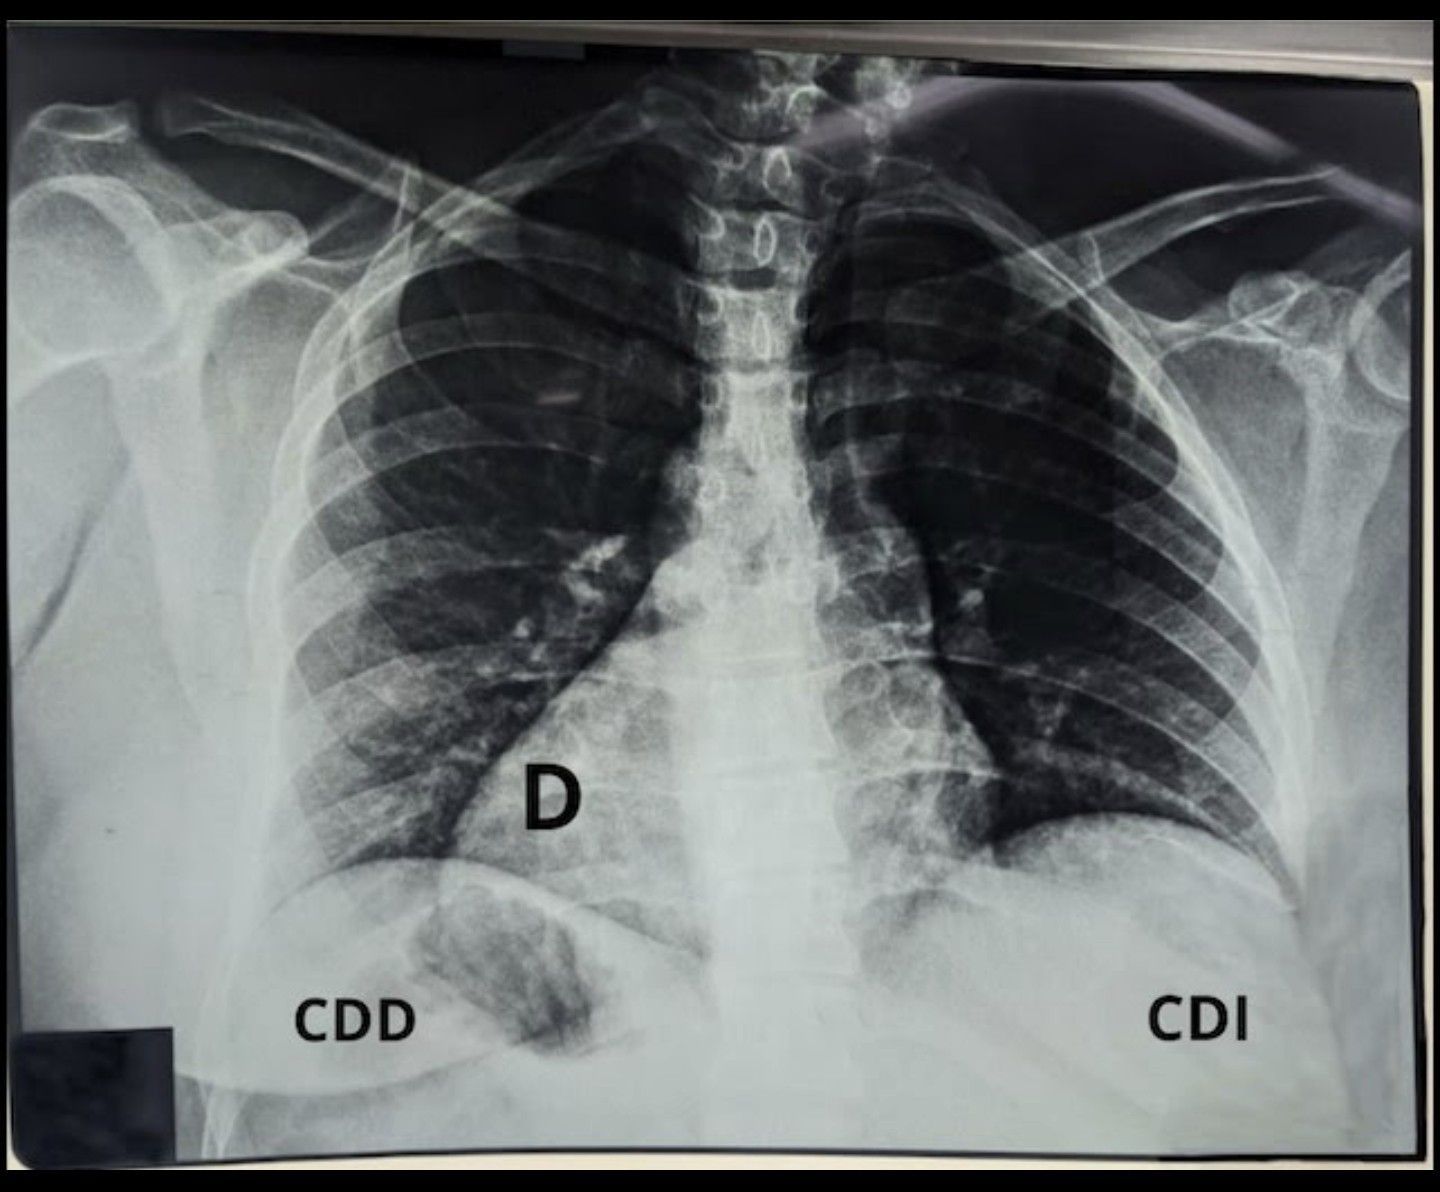

Situs inversus totalis (SIT) is a rare congenital malformation characterized by the complete reversal (transposition) of the normal location of the thoracic and abdominal organs. SIT is a very rare condition, with the incidence rate in humans estimated to be 0.01–0.02%, within which there is an equal prevalence among males and females. The exact causes of SIT are unknown. As the mechanisms for asymmetry in vertebrates are being defined, a number of genes that express asymmetry in embryonic development are being identified that appear to play a critical role in determining the left–right axis and may be linked to the development of SIT. SIT does not typically affect quality of life or lifespan; however, it has been linked to cardiac and vascular alterations associated with increased risks of heart, spleen and hepatobiliary malformations. SIT is also associated with Kartagener’s syndrome, which is an autosomal recessive disorder also known as primary ciliary dyskinesia.